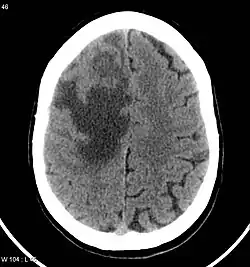

Brain CT scan showing CNS metastasis from the breast, the primary source.

CNS metastasis is the spread and proliferation of cancer cells from their original tumour to form secondary tumours in portions of the central nervous system.[1]